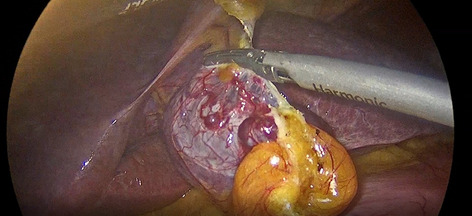

Background: Advances in artificial intelligence (AI), machine learning, and sensors are now the driving force in innovation in robotic assisted gastrointestinal surgery. We have previously published a modular step-up approach for safe introduction of robotic assisted minimally invasive esophagectomy (RAMIE), defining 6 different phases of the surgery. As anastomotic leak depicts one of the most severe and early postoperative complications and is considered a benchmark for the quality of the esophagectomy we are aiming to apply artificial intelligence and machine learning tools to successfully implement an automated surgical phase recognition for RAMIE in addition to using the same AI techniques to detect surgical quality metrics, focusing on the anastomotic phase as a crucial surgical phase.

Methods: Starting 01/2019, we implemented a standardized robotic anastomotic technique using a circular stapler and ICG (indocyanine green) for our RAMIE cases at our academic center (Fig. 1). Video material of standardized RAMIE cases was recorded and criteria for selection of suitable videos for annotation were defined. Those included high video quality and performance of a standardized anastomotic phase. Anastomotic phase was defined to begin when the cautery hook touches the esophagus, and the esophagus is divided. Next a monofilament purse string suture is performed robotically. One 12-mm assistant trocar is then removed, and this incision is extended to a mini thoracotomy with a standardized length of 7 cm. The stapler head is inserted and sutured into the esophageal stump using the prepared purse string suture using the robotic instruments. Its end was defined as when the circular stapler head is successfully sutured in and the needle is cut off. Next, video annotation was performed using pixel annotation for tool identification and vector annotation for identification of instrument direction and head of the used instrument (Figs. 2 and 3).

Results: Since 01/2019 a total of 94 RAMIE cases were performed, all cases were set up to be recorded. Successful and complete video recording was found in 60% of cases. N = 15 videos were evaluated for video annotation. 60% (n = 9 videos) were found suitable for annotation as defined above. Reasons for exclusion were failure of standardization of the anastomotic phase such as change of circular stapler size, additional lymphadenectomy, additional swap in the picture, rupture of suture, incomplete video or minor bleeding. Mean time of the anastomotic phase was 27.39 min (range 22.03 min- 30.97 min). The robotically performed part of the anastomotic phase showed a mean of 18.19 min, compared to a mean of. 9.2 min of mini-thoracotomy and stapler head introduction. This leads to a total of 163.72 min of video data suitable for annotation. Interestingly, annotation was found to be more time consuming than previously published as 4 instruments were actively used compared to 2 for e.g. in robotic urological surgery. An average of 6 min per picture were found for pixel annotation, compared to 3 min for vector annotation.

Conclusion: Video standardization is more important than ever when implementing artificial intelligence tools. Standardization may include factors such as quality, resolution, frame rate, however, also includes technical aspects of the operative technique. Interestingly, even though a standardized approach was applied, only 60% of all recorded videos were found to have a truly standardized anastomotic phase.